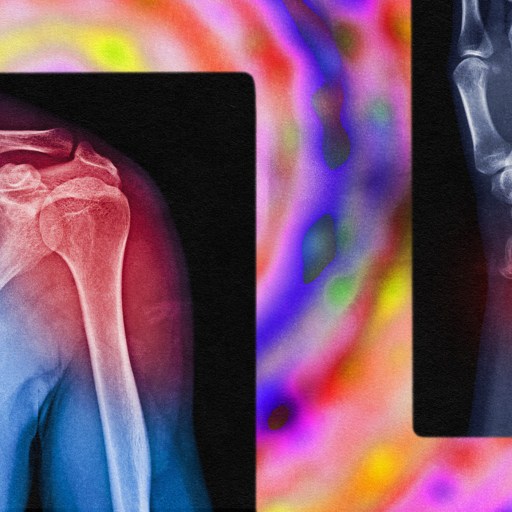

X-ray images of a shoulder and a wrist with highlighted areas in red indicating injuries or inflammation, set against a colorful, abstract background.

Fixing chronic pain in the body may sometimes require a treatment focused on the brain.